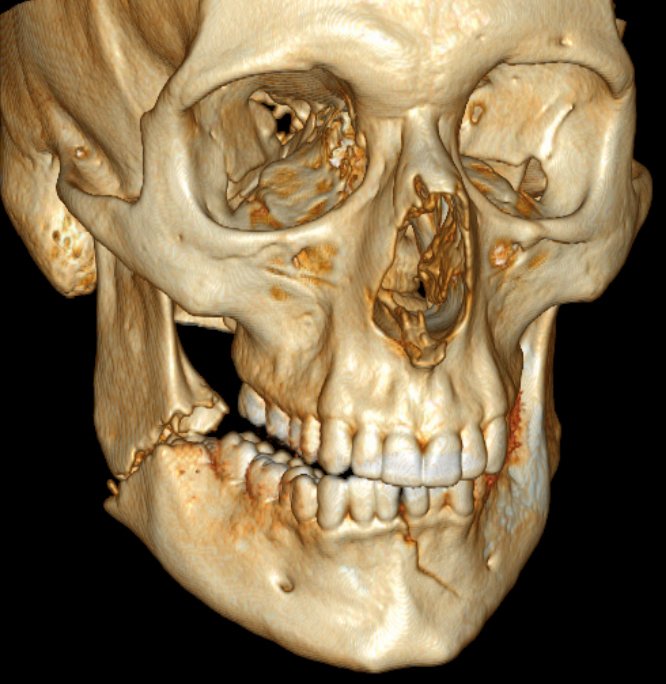

٢/ كسور عظام الوجه والفك:

يعالجها طبيب جراحة الوجه والفكين .

٥/ كسور عظام الجمجمه: يعالجها طبيب جراحة المخ والاعصاب.